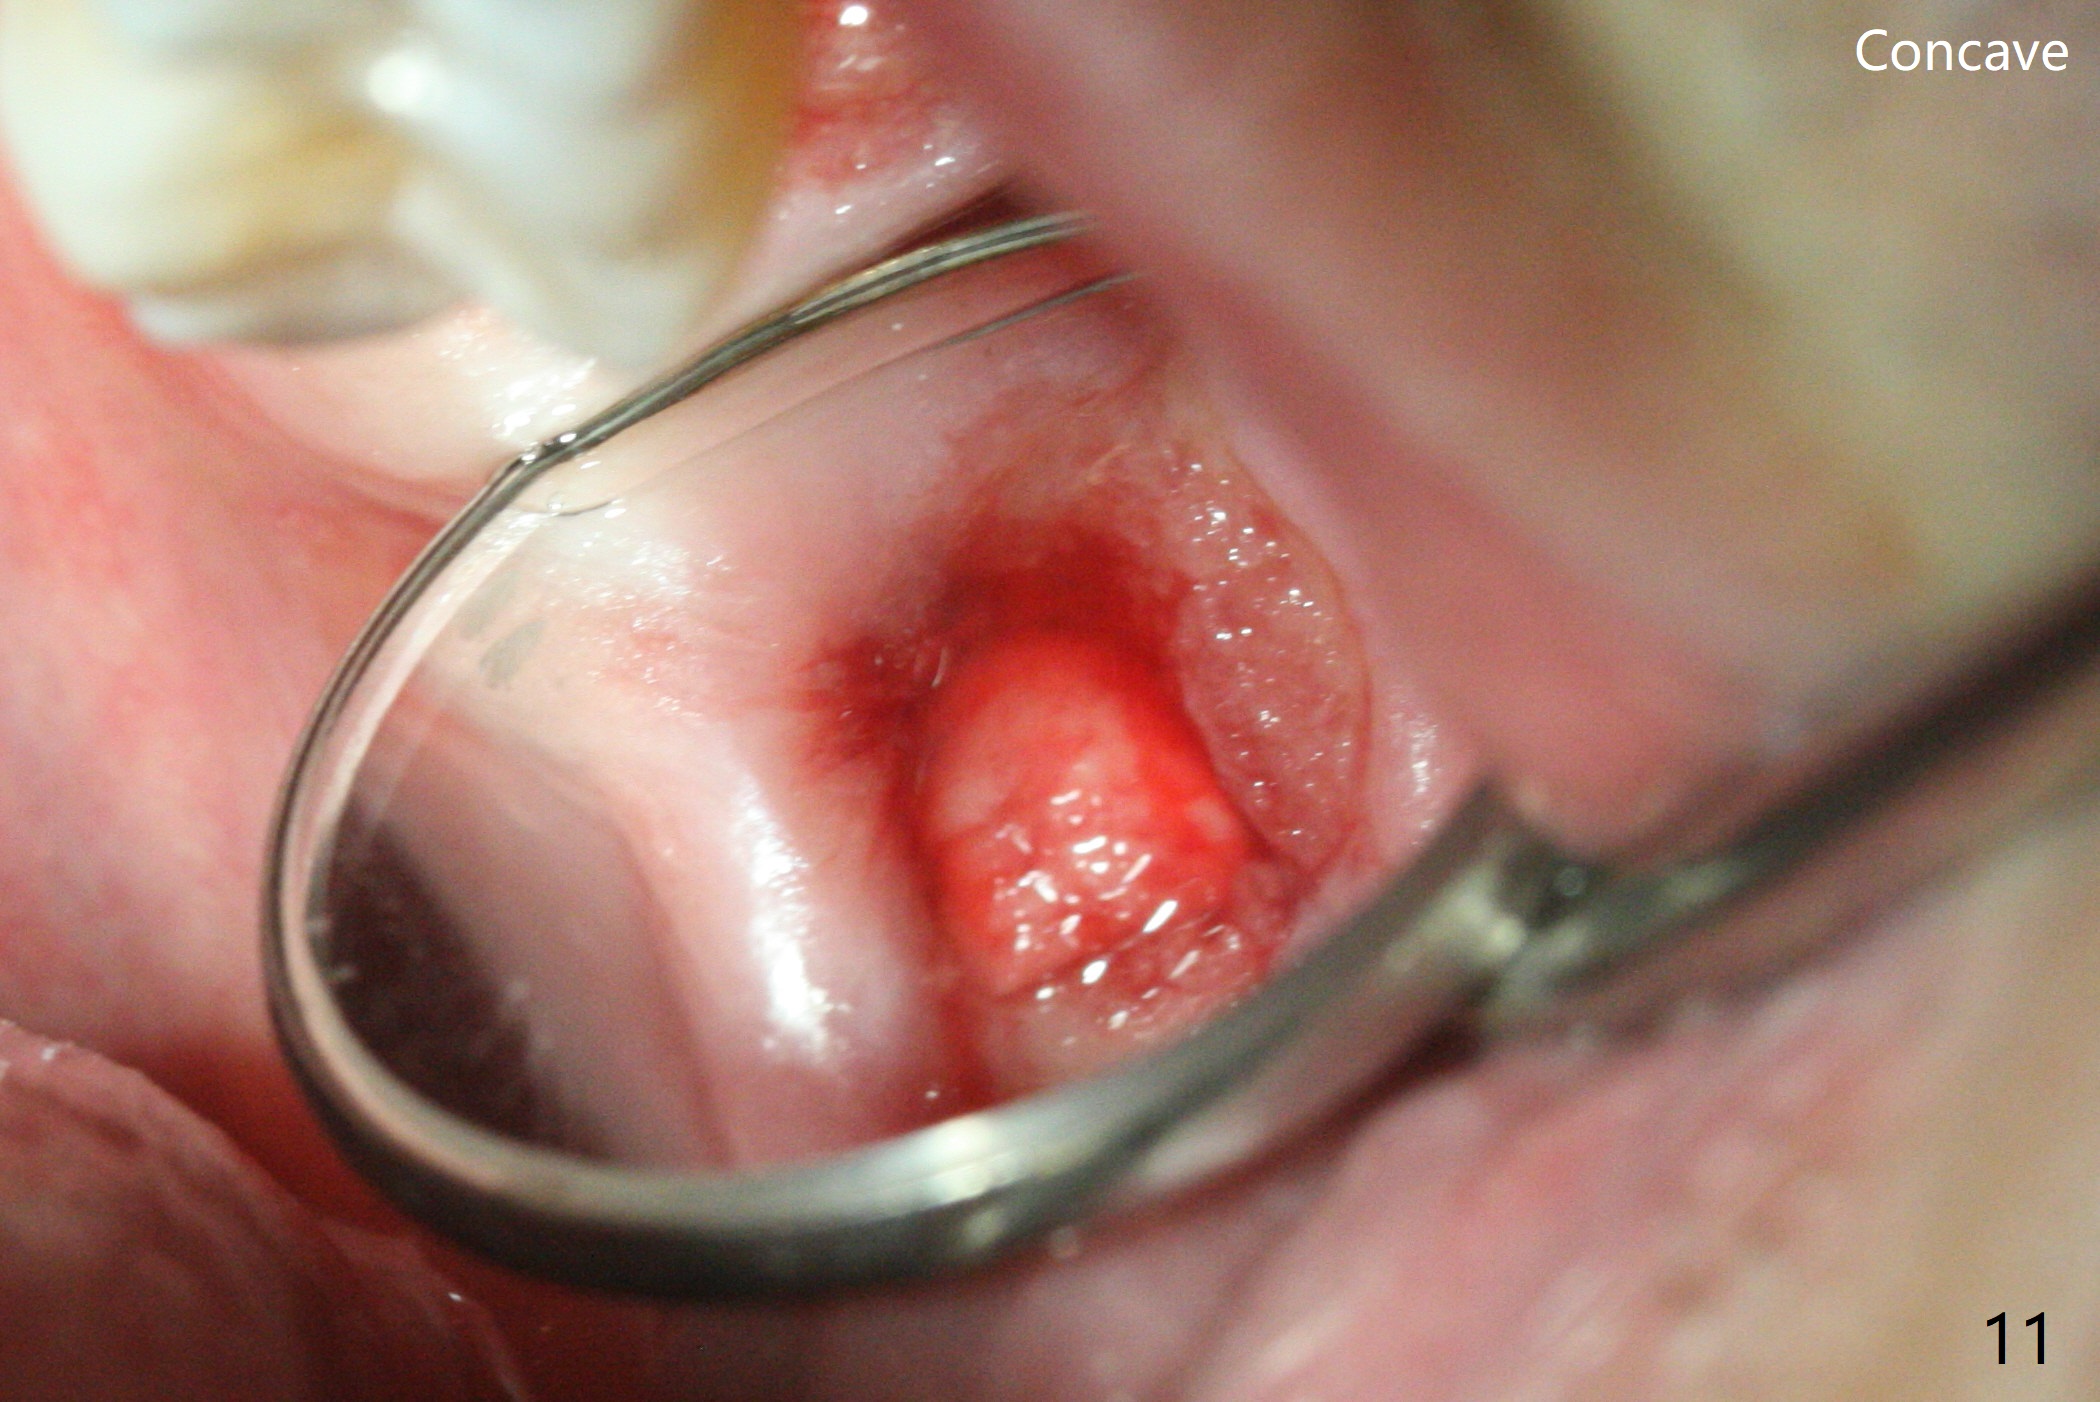

After 4.5x7.3 mm drill with 3 O-rings at #15, use 2.2x7.3 mm one with 2 O-rings. The sinus floor feels like to be perforated, but perio probe does not find the perforation. Nose blowing does not reveal air leakage. It seems fine when 3.0x7.3 mm one with 2 O-rings is being used. The sinus membrane perforates when Magic Sinus Lifter is used. Mixture of autogenous bone (from drills) and allograft does not stick to the periosteal elevator (Fig.1). Forty-minute centrifuge leads to separation of serum (Fig.2 S) from Red Blood Cell layer (R). The separation of the top tube is incomplete with RBC invade the serum layer in a few second (Fig.3 arrow). While the serum layer of the bottom tube is prepared for PRF membrane, a part of the serum layer of the top tube is withdrawn to make sticky bone (Fig.4). The top tube returns to the centrifuge for another 30 minutes to make the second PRF membrane. The first PRF membrane is inserted into the osteotomy and pushed into the sinus with empty feeling, followed by the sticky bone and last by the 2nd PRF membrane. A 5x7.3 mm implant is placed with ~ 10 Ncm, followed by a 6.8x4 mm healing abutment (Fig.5,6 (retrospectively healing screw should be used to reduce sinus-oral communication)). There is no mushroom in the sinus, but hopefully the sticky bone will stick to the bottom of the sinus for maturation. Sinus surgery precaution is provided. Next time tap or dummy implant will be used for sinus lift after initial osteotomy with guide. In fact the patient with diabetes under control has mild cold. The procedure should have been canceled. There is no postop nasal hemorrhage or discharge. The patient returns nearly 8 months postop. The wound is infected. The healing abutment is changed to a healing screw with oral antibiotic. Two weeks later, the area remains infected with symptoms (Fig.7-9). The healing screw is not covered completely. After implant removal, the sinus membrane is perforated. A piece of collagen plug (preferably Osteogen plug) is inserted (Fig.10,11). Because of the concavity, bone graft seems necessary when the wound heals. One week later, perimplantitis develops at #2. The patient is ready for the 3rd placement 1 year 5 months post last implant removal (Fig.12). The bone is 1.8 mm thick, apparently composing of 2 fused cortical plates. Make an incision for both external and internal sinus lift with retraction. Find the old guide to start osteotomy including bone trimmers and use Magic Lifter. If the membrane is broken, open the lateral window to repair with PRF.